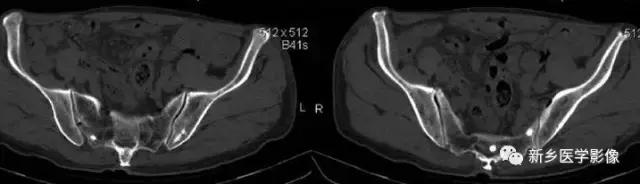

输精管钙化

主要表现为盆腔内对称性小钙化灶。